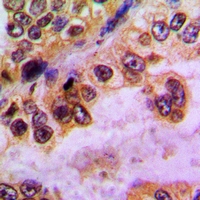

分类: 科研抗体货号: P43575别名: fetal hemoglobin; HBGA; HBGR; HBG-T2; HSGGL1; PRO2979; TNCY; HBG-T1应用: WB,IHC反应种属: Human